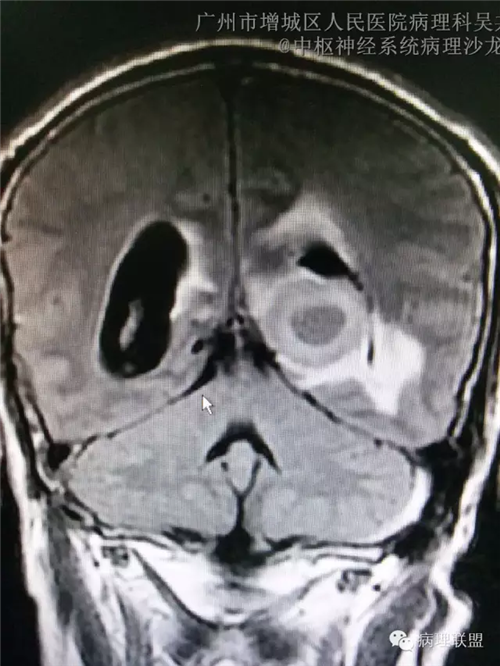

脑部影像学结果: